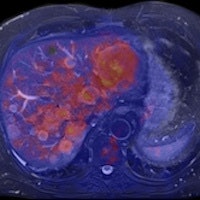

When the doors of the ECR 2011 technical exhibition burst opened this morning, a host of surprises and innovations awaited congress attendees. Arguably the biggest highlight of all is the first PET/MR system ever displayed at the Austria Center, and it looks certain to attract massive attention and interest over the next four days.

A combination of MRI and PET has long been considered as the logical next step in the evolution of imaging modalities, but industry has struggled to deal with the formidable technical challenges of achieving a happy marriage between the two approaches, notably the difficulties of developing a PET detector capable of coping with the powerful static and dynamic magnetic fields generated by the MR coils. GE Healthcare made the first important move in developing the software needed to integrate data acquired through sequential scans made using the two modalities. Then Philips brought the two main items of hardware alongside each other, linked by a revolving table for easy patient transfer, and the company installed the first European system in a hospital in Geneva in April 2010. Now Siemens' engineers have successfully merged the two modalities in a single unit, dubbed the Biograph mMR, which the vendor plans to launch commercially later this year.

In the meantime, radiologists will be able to examine the prototype on display in the technical exhibition, and if they are lucky, they will get to talk to Dr. Markus Schwaiger and his colleagues from the Klinikum rechts der Isar at the Technical University in Munich. The group has been given the privilege of putting the new machine through its paces.

Dr. Alexander Drzezga, from the university's department of nuclear medicine, has been responsible for setting up the system, which was delivered in November 2010. It is currently being used to scan up to five patients a day, but that number is likely to grow as the Munich team explores the limits of the unit's clinical potential. "Many neurological conditions are suitable for evaluation with PET/MR, including neurodegenerative disorders, dementia, epilepsy, and brain tumors. With regard to evaluation of the cardiac system, combined imaging of PET and MR may also show diagnostic advantages, while inflammation and vascular conditions are also areas of interest," he explained.

Drzezga believes that combining the two modalities offers a number of clinical advantages, not least in eliminating the need for separate diagnostic examinations. Furthermore, the exact anatomical registration of structural and functional/molecular information may improve allocation of suspect findings and improve image quality, for example by motion correction of regions of the body that do not remain rigid during examination. The Munich team will also be exploring how the performance of PET/MR compares with that of PET/CT. There is some evidence that the superior soft-tissue contrast achievable with the newer system will offer significant benefits, even before physicians consider the safety issues involved with any radiation-based imaging technology such as PET/CT, Drzezga suggested.

The Biograph mMR is based on the Verio 3-tesla MR system with a 70-cm bore that provides enough space to position the PET detector ring and its solid-state photodiodes. In getting the two modalities to work alongside each other, the hybrid molecular MR system can scan the whole body in as little as 30 minutes, compared with an hour or more needed for sequential examinations. The machine also incorporates Siemens' TIM (total imaging matrix) technology, which seamlessly integrates multiple coil elements and radiofrequency (RF) channels and can reduce examination times by up to 50%, according to the vendor.